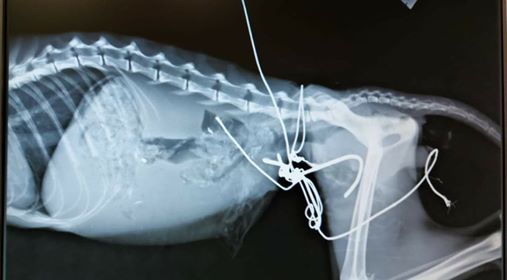

Τα νέα είναι ευχάριστα για το γατούλη που βρέθηκε αυτές τις μέρες στην περιοχή λίγο πιο πάνω από το Βασδέκειο, Αδραμύτιου με Πριάμου, στο Βόλο, δεμένος με σύρμα, το οποίο είχε χωθεί στην κοιλιά του. Το ζώο, το οποίο είχε σηψαιμία και βρισκόταν σε άθλια κατάσταση, μετέφεραν σε κλινική και ανέλαβαν οι εθελοντές της Φιλοζωικής Ομάδας Βόλου https://www.facebook.com/fiovol/.

Η κατάστασή του ήταν κρίσιμη. Η τελευταία όμως ανάρτηση της ομάδας κάνει λόγο για καλυτέρευση της υγείας του καθώς το ζώο ανταποκρίνεται στην αγωγή. Το χειρουργείο έκανε ο κτηνίατρος Φιλήμων Διαμαντής.